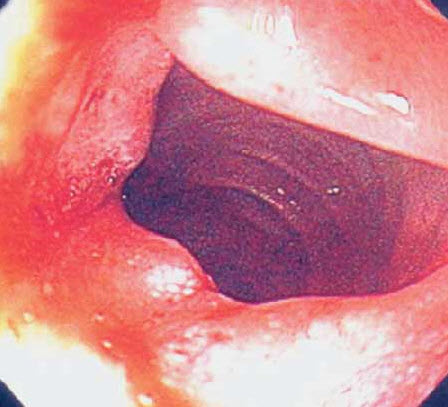

Three months before the current symptoms developed, the patient had an episode of upper GI bleeding manifested by melena; there was no change in the hemoglobin level. An esophagoduodenoscopy revealed a "clean-based ulcer" in the descending portion of the duodenum (Figure 1). Biopsy of the ulcer was not performed at that time. Antral biopsies were negative for Helicobacter pylori. Pantoprazole (40 mg/d) was prescribed, and the patient was instructed to discontinue aspirin.

Diagnostic studies. A CT scan of the abdomen reveals a markedly dilated stomach with an obstructive mass in the descending portion of the duodenum; these findings are consistent with gastric outlet obstruction (Figure 2). In addition, biliary and pancreatic ductal dilatation and multiple liver masses are noted. Esophagoduodenoscopy shows near complete luminal obstruction by the mass (Figure 3). The scope is unable to pass beyond the markedly narrowed lumen. Results of biopsies of the duodenal mass reveal moderately differentiated invasive adenocarcinoma (Figure 4).